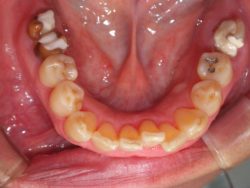

(術前)

年齢・性別:70代 女性

主訴:左右下の奥被せ物外れた

診断:左右6 C4(残根状態)

治療内容:下顎左右 6 骨造成

下顎左右 6 インプラント

治療期間:9カ月

骨造成:インプラント植立後

担当医からのコメント:左右の咬合平面揃え、患者様の協力度も高く、順調に経過しているケースです。